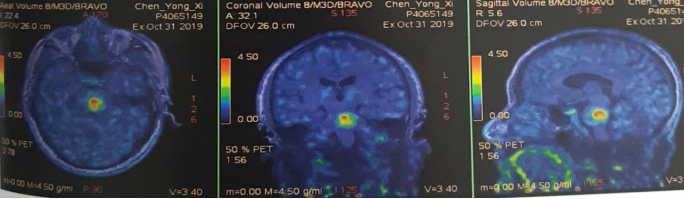

脑部蛋氨酸PET示:脑桥结节,蛋氨酸代谢异常增高,SUVmax 4.51,考虑转移性恶性肿瘤。

影像科、神经内科会诊,考虑脑部病灶为肠癌转移病灶。

脑干转移病变,合并瘤卒中,周边水肿。

处理:2019.11.5至2019.11.10行射波刀放疗,DT 20GY/4F,同步替莫唑胺化疗。

处理:再次射波刀追加剂量,DT 20GY/4F,贝伐珠单抗200mg治疗一次。

效果:患者脸部麻木及右侧肢体麻木症状改善明显,肌力IV级,可独自行走。